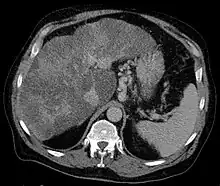

Axial CT showing varices of the fundus in liver cirrhosis with portal hypertension